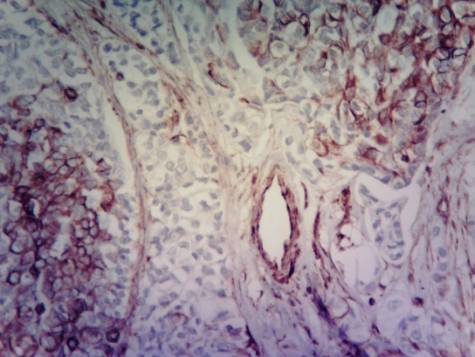

Leukocyte infiltration in tumour and

tissue around the tumour is characterized by an accumulation of cells. The

degree of positive expression of vimentin can be divided into 4 groups. I group

- cells with negative expression of vimentin; ІІ group - with few positive

expression of vimentin; III group - characterized by a moderate expression of

vimentin; IV group - with a pronounced expression of vimentin. The intensity of

color from 0 to III scores. Group I - cells colored with hematoxylin and have no

shades of brown (0 points), second - on a background of blue color visible

brown shade (1 point), III - color brown (2 points), IV reddish-brown (3

points).

Carcinoma

ductal breast cancer. Tissue around

the tumour. Accumulation of

cells of leukocyte infiltration with different degree of expression.

Immunohistochemical technique for vimentin.